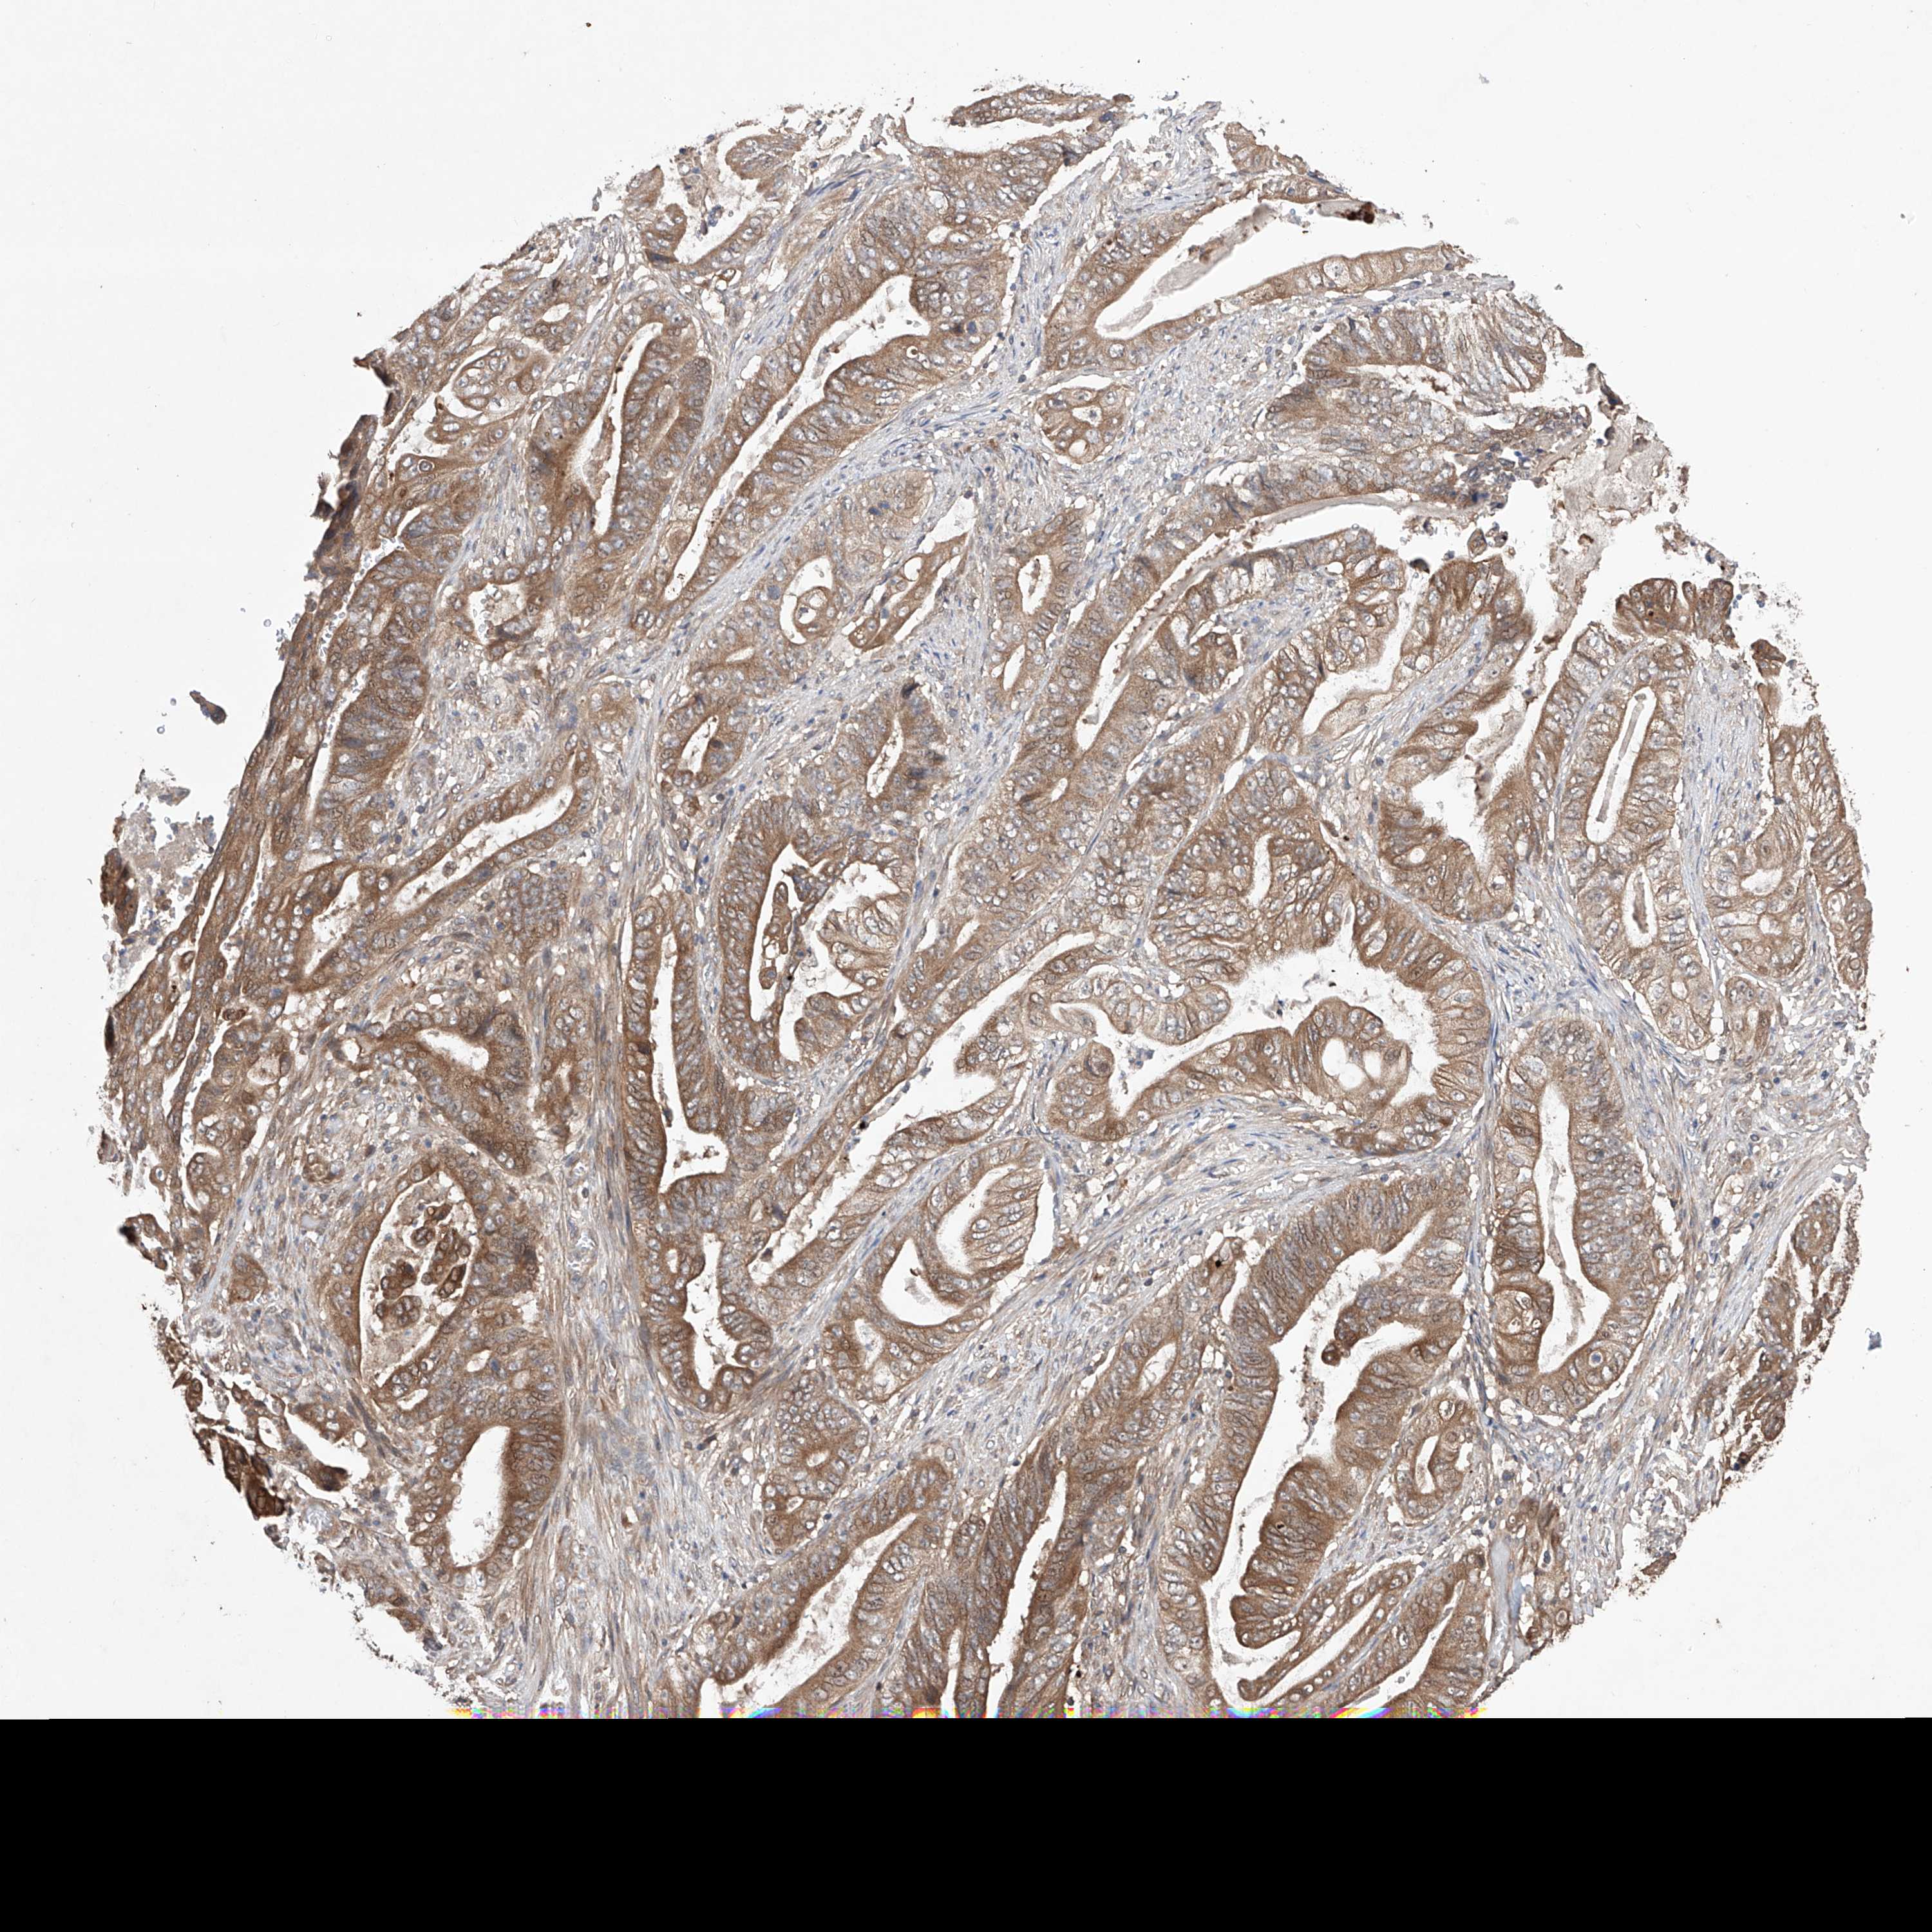

STOMACH CANCER - Protein expressioni

A mouse-over function shows sample information and annotation data. Click on an image to view it in a full screen mode. Samples can be filtered based on level of antibody staining by selecting one or several of the following categories: high, medium, low and not detected. The assay and annotation is described here.

Note that samples used for immunohistochemistry by the Human Protein Atlas do not correspond to samples in the TCGA dataset.

Antibody stainingi

Antibody staining in the annotated cell types in the current human tissue is reported as not detected, low, medium, or high, based on conventional immunohistochemistry profiling in selected tissues. This score is based on the combination of the staining intensity and fraction of stained cells.

Each image is clickable and will lead to virtual microscopy that enables deeper exploration of all samples and also displays staining intensity scores, fraction scores and subcellular localization as well as patient and tissue information for each sample.

Antibody HPA030060

Antibody HPA030061

Staining

High

Medium

Low

Not detected

Intensity

Strong

Moderate

Weak

Negative

Quantity

>75%

75%-25%

<25%

None

Location

Nuclear

Cytoplasmic/membranous

Cytoplasmic/membranous,nuclear

Adenocarcinoma, NOS